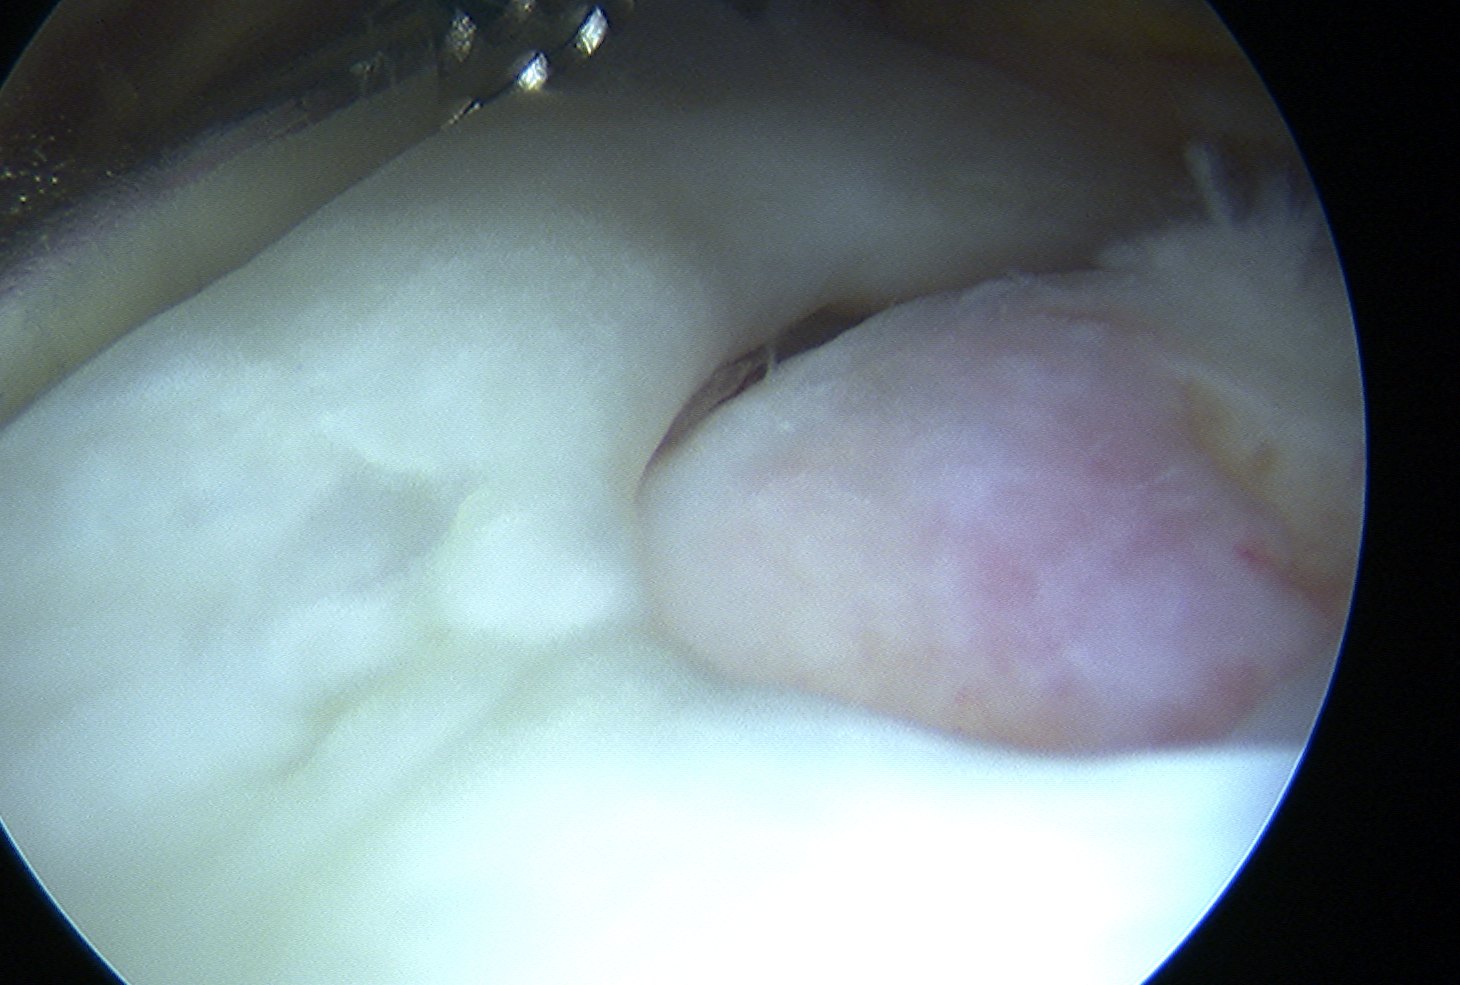

Preparation

Prepare insertion

- debride tendon edges

- debride footprint to punctate bleeding

Assess tendon mobilisation / tear geometry

Repair

Large U shaped tendon

- insert margin convergence sutures

Place medial row anchors

- anterior first

- insert 18 G spinal needle and ensure good angle

- just medial to articular cartilage